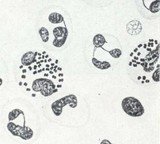

• Слика приказује бактерију гонокок која је изазивач полне болести трипера а на препарату је представљен у виду интрацелуларних мрља у облику кафе.